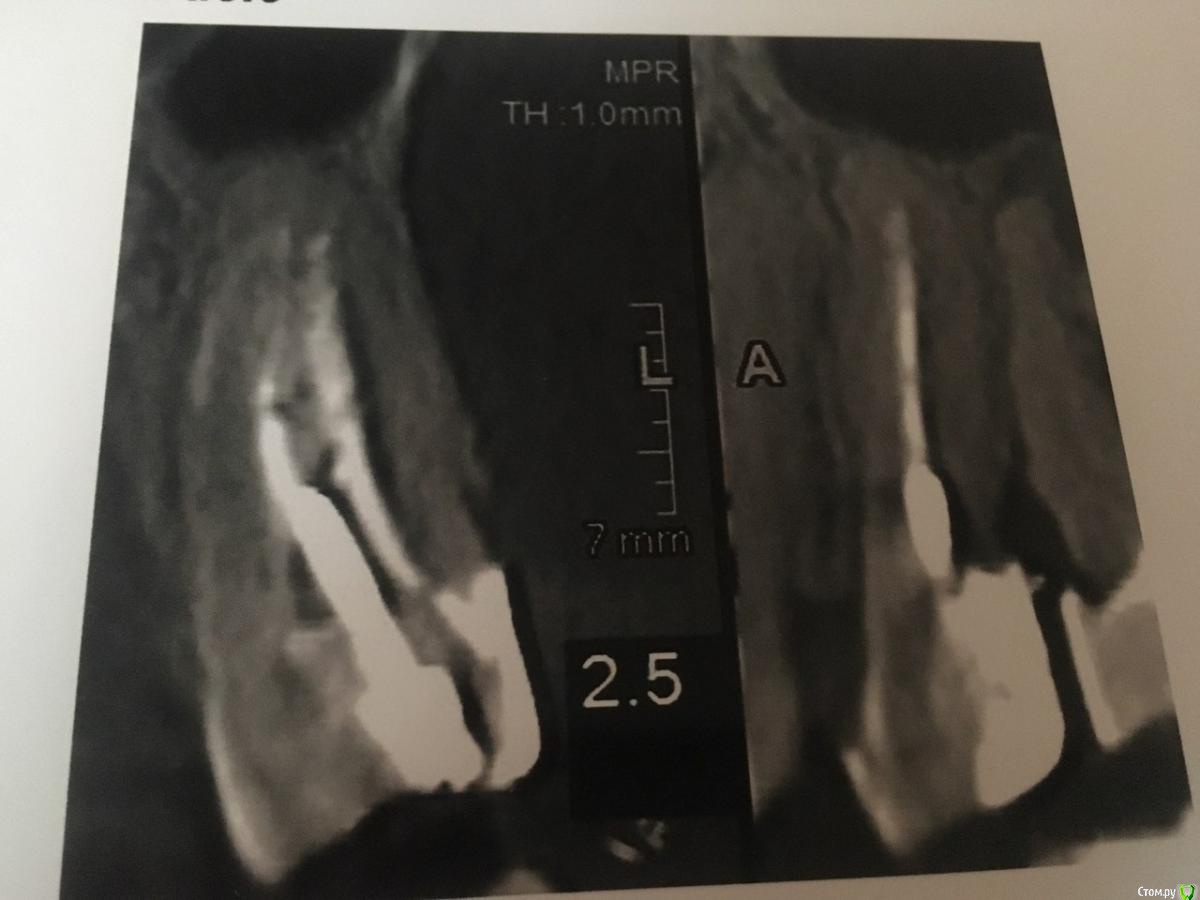

В течении  года от зуба опустилась десна и там проглядывается прозрачно-черный корень и очень быстро на 5 и 4-ки обазовались черные пятна.  Сделала КТ. Теперь стоит вопрос долгое  лечение или удаление.Врач говорит все будет видно при вскрытии. Если лечение то долгое и без гарантий.   Мне кажется от корня там мало что осталось,судя по цвету и по тому как быстро испортились рядом стоящие зубы. Может проще не лечить,установить имплант?

Правда один врач сказал,что то вроде убыли костной ткани и имплант удержать будет не чем,кроме того сужение верхней челюсти, рецессия десны и стирание в пришеечной области из за прикуса. В заключении кт -пародонтопатия легкой степени тяжести.